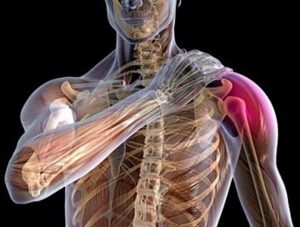

Вывих – это смещение суставных костных окончаний, которое вызывает неправильную функцию сустава. При этом полностью отсутствует контакт между соединяющимися поверхностями. Вывих плечевого сустава – серьезная травма. По МКБ 10 ее код – S43.0.

Плечевой сустав отвечает за подвижное соединение руки с ее поясом, который формируется ключицей, лопаткой, мышцами, связками, сухожилиями. Вывих может произойти совместно с травмами этих костей, растяжением связок.